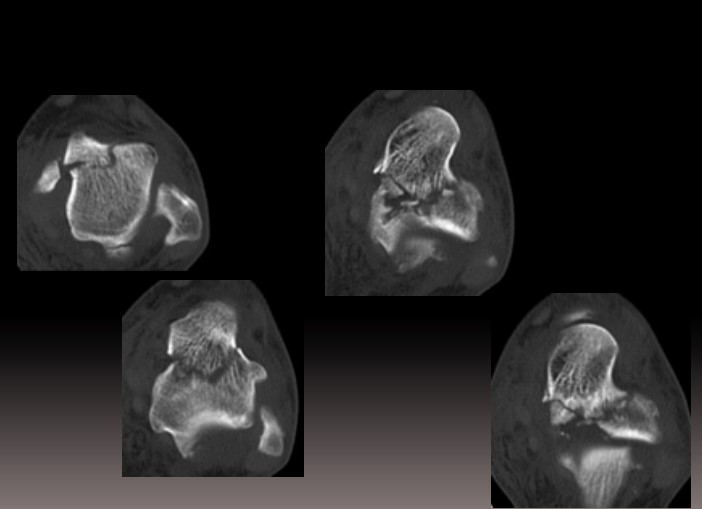

Компютерна томографія (КТ) є золотим стандартом у діагностиці переломів таранної кістки, дозволяючи детально оцінити характер перелому, ступінь зміщення фрагментів, стан суглобових поверхонь та планувати оперативне втручання. КТ-ангіографія може надати додаткову інформацію про васкулярний статус.

Методи фіксації: Сучасні методики включають остеосинтез гвинтами (канюльованими або кортикальними), пластинами або їх комбінацією. Анатомічна репозиція суглобових поверхонь є критичною для профілактики посттравматичного артрозу. Фіксація має забезпечувати достатню стабільність при мінімальному порушенні васкуляризації.

Артроскопічний контроль: Сучасні протоколи рекомендують артроскопічну асистенцію для верифікації якості репозиції суглобових поверхонь та видалення інтраартикулярних фрагментів.